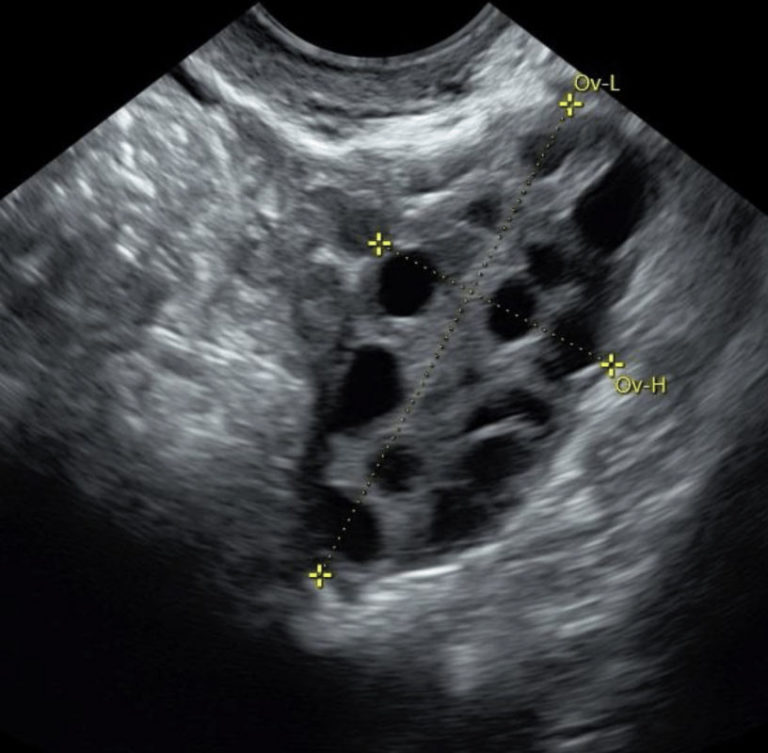

Follicle tracking scans may be required if you are undergoing fertility treatments including IVF or Clomiphene treatment.

Follicle tracking uses transvaginal ultrasound to track the development of egg-containing follicles within the ovary from an immature state to a mature state.

You may be required to have 2-3 follicle tracking scans over the course of your menstrual cycle to assess the number of follicles and rate of growth. The timing of the scans will be determined according to your menstrual cycle and the rate of growth seen in the follicles.